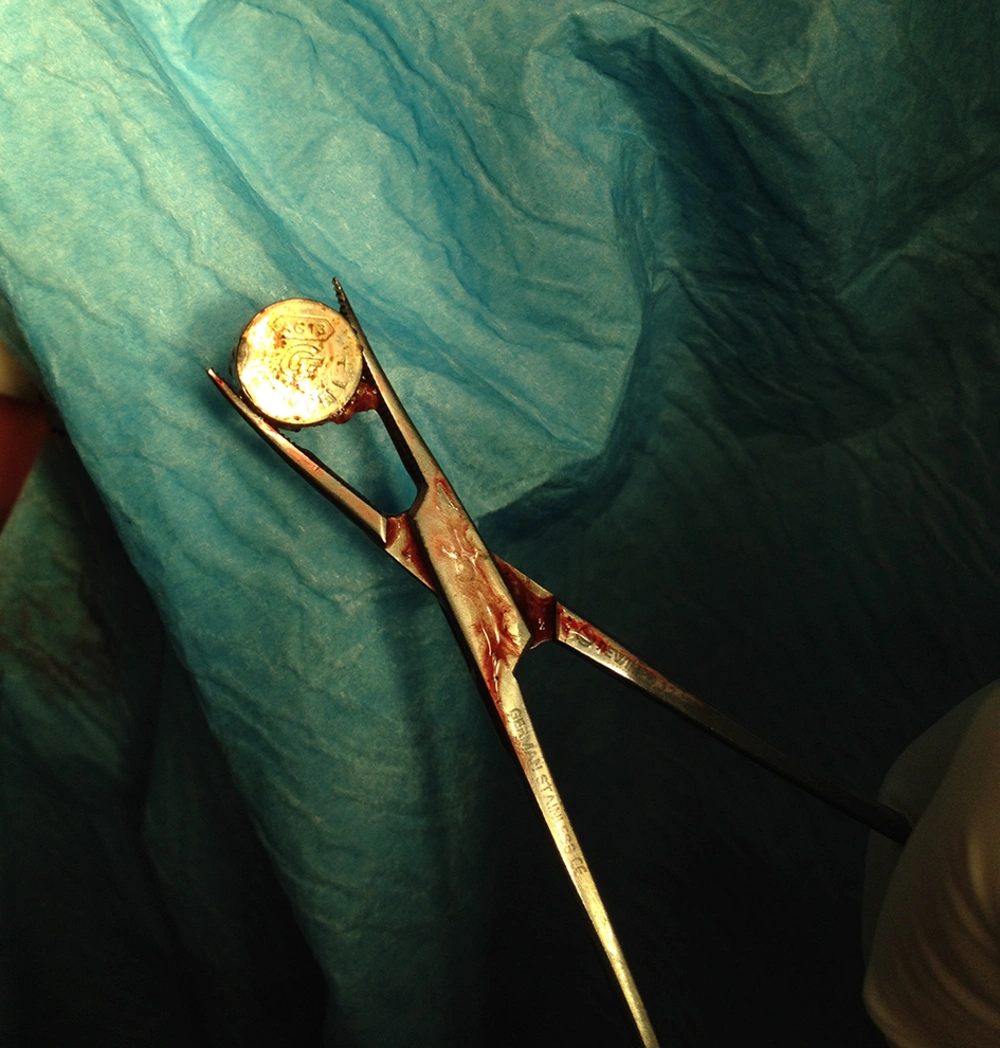

The patient was admitted for examination under general anesthesia. First we performed cystoscopy by a 6 Fr. cystoscope, but we did not find any bladder abnormalities. Furthermore, the vaginoscopy confirmed a round metal object embedded to the posterior fornix covered with necrotic tissue and surrounded by sever vaginal burn. Following vaginal irrigation by normal saline through the cystoscope the button battery was visible and the battery was pushed and fixed upward by a digital rectal maneuver in order to be grasped by Mosquito forceps and removed following installation of 5 mL of sterile lubricant gel by gentle traction (Figure 2). The object was a discolored 1 cm diameter battery. Repeated gentle vaginoscopy confirmed a type III coin shaped burn with no fistula to the rectum. The hymen was elastic and intact following removal of the foreign body. We finished the procedure following vaginal irrigation with diluted povidone-iodine solution and installation of gentamycin eye ointment into the vagina. Besides, we prescribed laxative (milk of magnesia) in order to facilitate a soft stool rectal passage. During her post-operative days she did not have fever or any systemic signs.